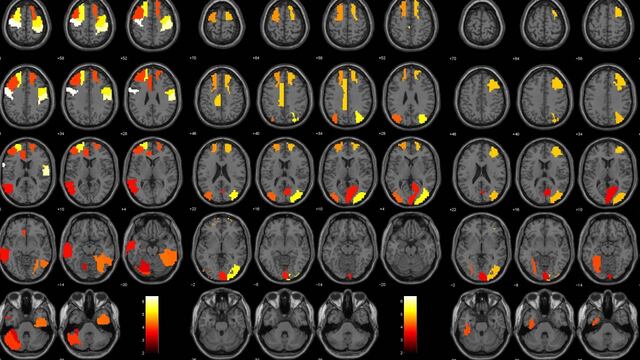

Un nuevo estudio sugiere que un error en el software para hacer imágenes por resonancia magnética funcional (fMRI, por sus siglas en inglés) podría invalidar al menos 40,000 documentos, abarcando los últimos quince años de investigación cerebral.

El problema principal es el “cómo” los científicos han usados los escaneos de fMRI para iluminar la actividad de ciertas regiones del cerebro. El procedimiento normal es que, dentro de un experimento, un individuo realice alguna actividad asignada mientras un campo magnético recorre su cuerpo, recolectando los pequeños cambios en el flujo sanguíneo del cerebro.

Estos pequeños cambios señalan a los científicos que cierta parte del cerebro está trabajando, como la región de la corteza insular que se activa al interactuar con un videojuego. Esta acción se ha relacionado con funciones cognitivas mayores como el proceso de lenguaje, empatía y compasión.

El problema es que los científicos están interpretando información de un máquina, no observando directamente el cerebro. Para comprobar su efectividad compararon los tres softwares mas populares de resonancia magnética funcional (SPM, FSL y AFNI) y aunque no encontraron muchas diferencias, los resultados que mostraban eran falsos-positivos el 70% de las veces.

De hecho el equipo sólo esperaba encontrar un 5% de falsos-positivos, lo que sugiere que algunos resultados son tan incorrectos que mostraban actividad cerebral donde no la había.